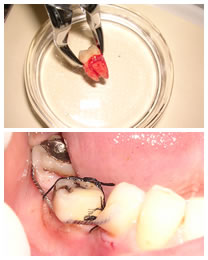

- 上の写真が、抜歯した上顎8番(親知らず)。

下の写真は、移植直後口腔内写真